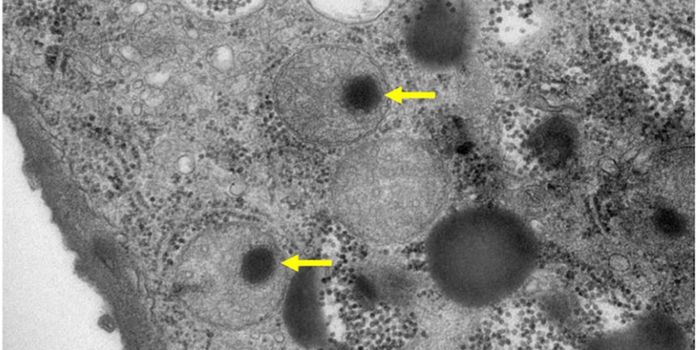

APR 19, 2022ImmunologyTuberculosis is caused by a bacterium, Mycobacterium tuberculosis, that is thought to have been around for about 150 mil ...